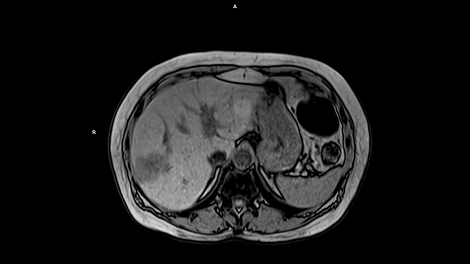

Whether it is head, neck, spine, abdomen or MSK – our clinical experts have complete confidence in the ability of MAGNETOM Free.Max to deliver excellent diagnostic quality for all these standard clinical MRI applications.